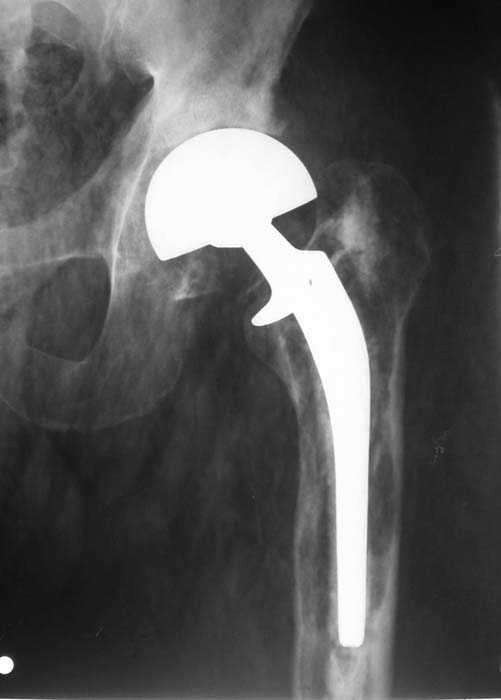

Мужчина, 39 лет.По поводу двустороннего асептического некроза головок бедренных костей последовательно выполнено тотальное эндопроезирование левого (1998 г), затем правого (1999 г) тазобедренных суставов.

С 2001 г отмечает нарастающие боли в левом бедре. Предполагается удаление протеза, удаление цемена из канала бедра, пластика дефекта бедренной кости.

Вторым этапом - тотальное бесцементное протезирование. Ваши предложения, мнения?

Нет никакого смысла делать операцию в два этапа. С чашкой все понятно - стандартный подход с установкой пресс-фит компонента. На бедре имеет

место перипротезный перелом В3 типа - т.е. перелом вокруг ножки с ее нестабильностью на фоне выраженного остеолиза. Решение - доступ к каналу

через перелом с удалением самой ножки, костного цемента и рубцовых тканей. Установка ножки дистальной фиксации (типа Solution), длину ножки

надо определить по шаблону. Минимальный контакт ножки с интактной костью - 6-8 см. Фрагменты проксмального отдела собираются на ножке

эндопротеза, дефекты костной ткани заполняются чипсами (аллографт) и фиксируются кортикальными аллографтами, уложенными дополнительно по типу

"вязанки хвороста" серкляжом. Мы имеем 8 или 10 подобных наблюдений и результатами довольны.